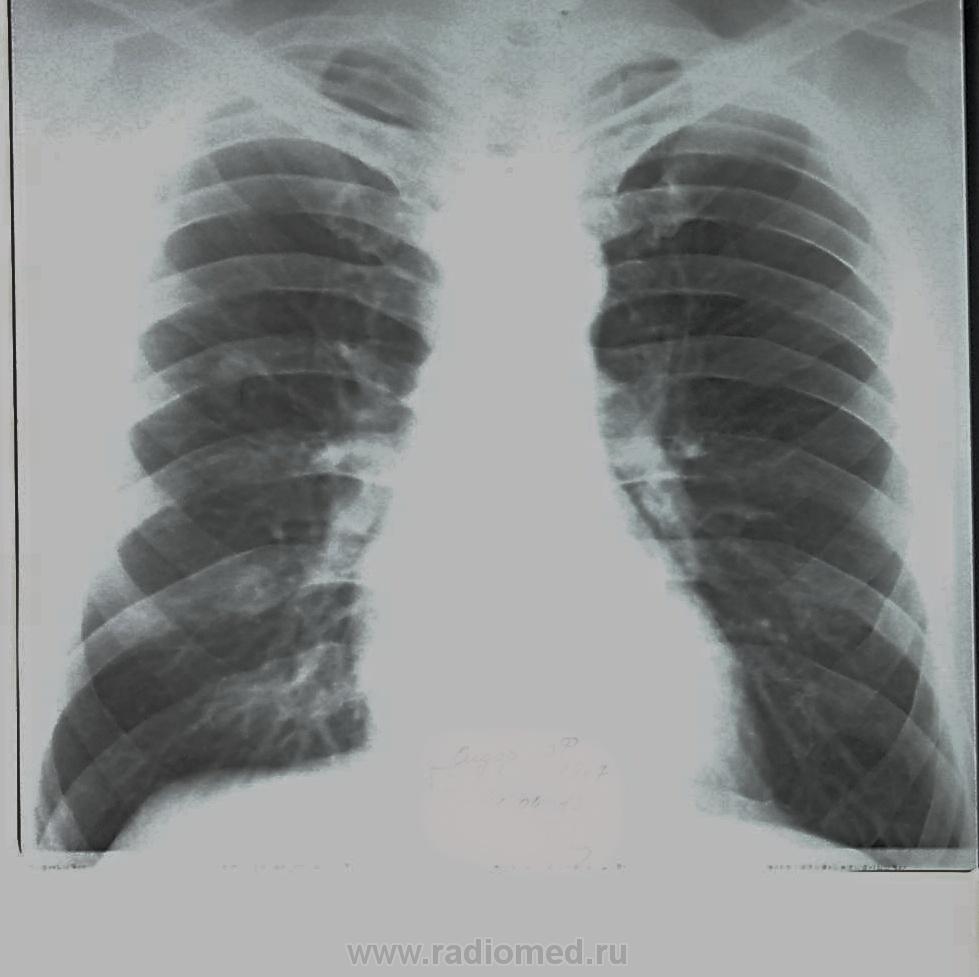

Направлен в ПТД, " очаговая тень справа". Что-то фтизиатр после 2нед. обследования стал "выталкивать" к онкологу.

Согласен полностью! Вы yes . По линейке поставил ТУБЕРКУЛО(Ё)МУ.  Мать -губерния потребовала контраст - отказал.( нет обоснования!) Это не обоснование -" нам не нравится". Предложил контроль после лечения.

Причина отказа: при "носовом" т.е. носом по снимкам КТ, просмотре - как бы участок кальциноза по периферии.  Так и заявил: " предположительно локальное обызвествление образования". Ну подождем.